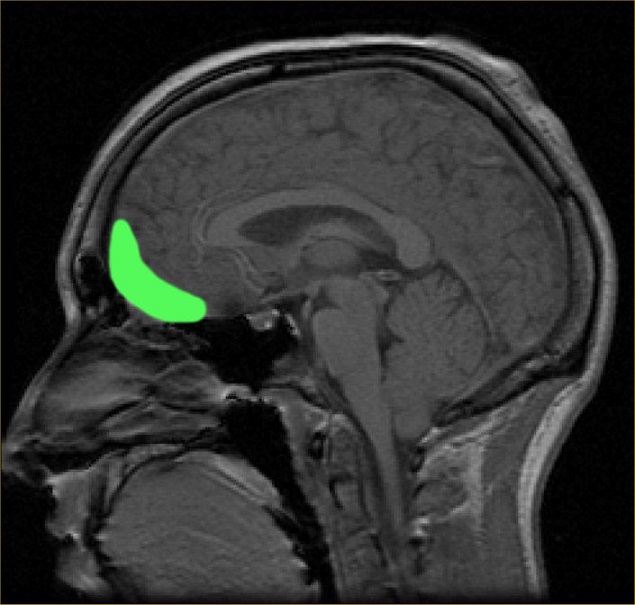

人类中间(与奖赏有关,OFC13)和侧面(与奖赏无关,OFC47/12)眼窝前额脑皮层网络,显示在忧郁症病患不同的功能连接。University of Warwick

这个成像技术能够显示出人类脑部受到忧郁症影响不同区块之间连接的活动,那就是中间和侧面眼窝前额脑皮层。侧面眼窝前额脑皮层与没有奖赏有关联,在忧郁症群的病患中,显示出相当强烈的连接。

如同研究小组所提,侧面眼窝前额脑皮层也和与自我感觉有关联的区块相连接。在那些受苦于忧郁症的人,这两个区块被发现有强烈的连接,或许解释了为什么有忧郁症的人经常有个人损失和自尊心低落的想法。